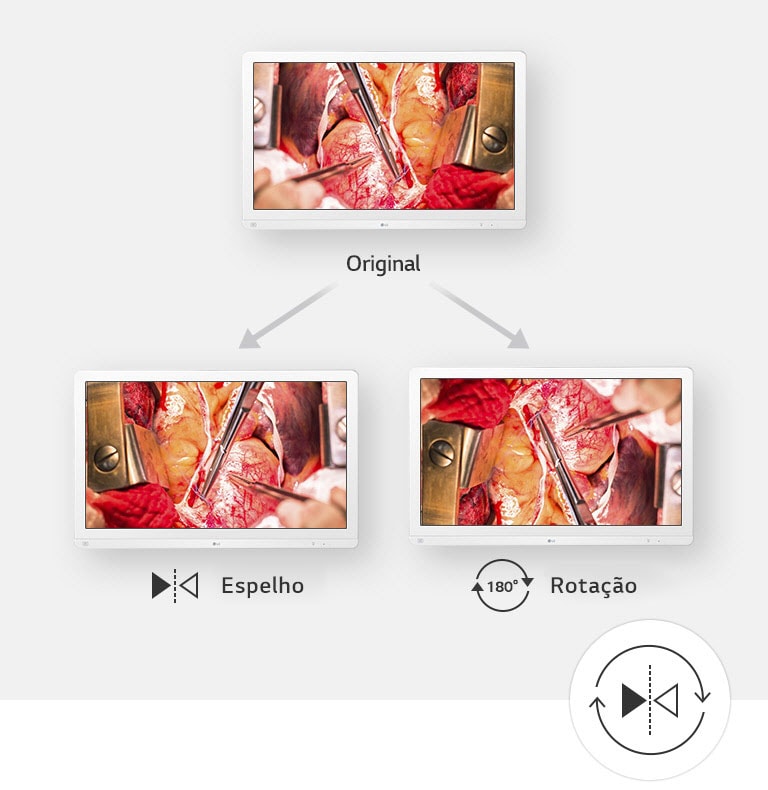

Modo Rotación y Espejo

SIM